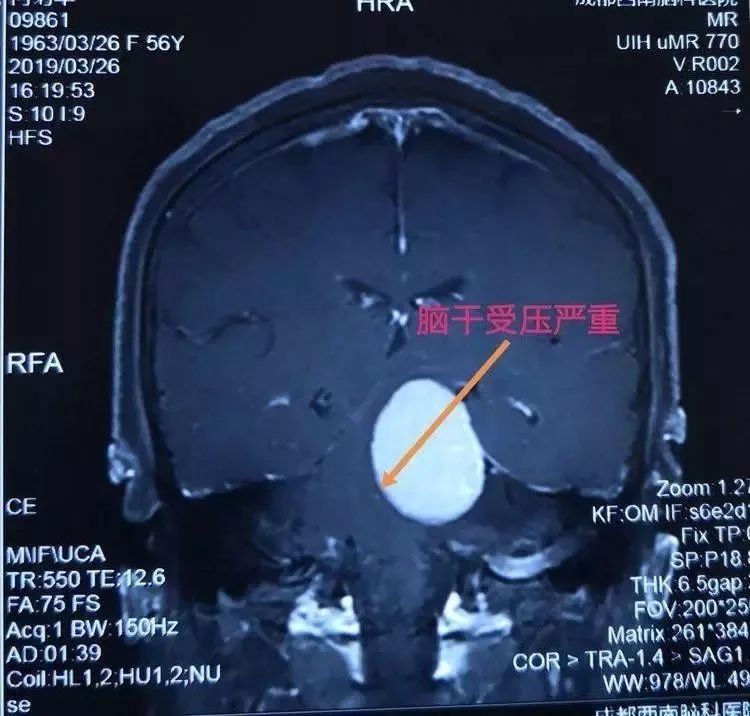

脑肿瘤磁共振影像